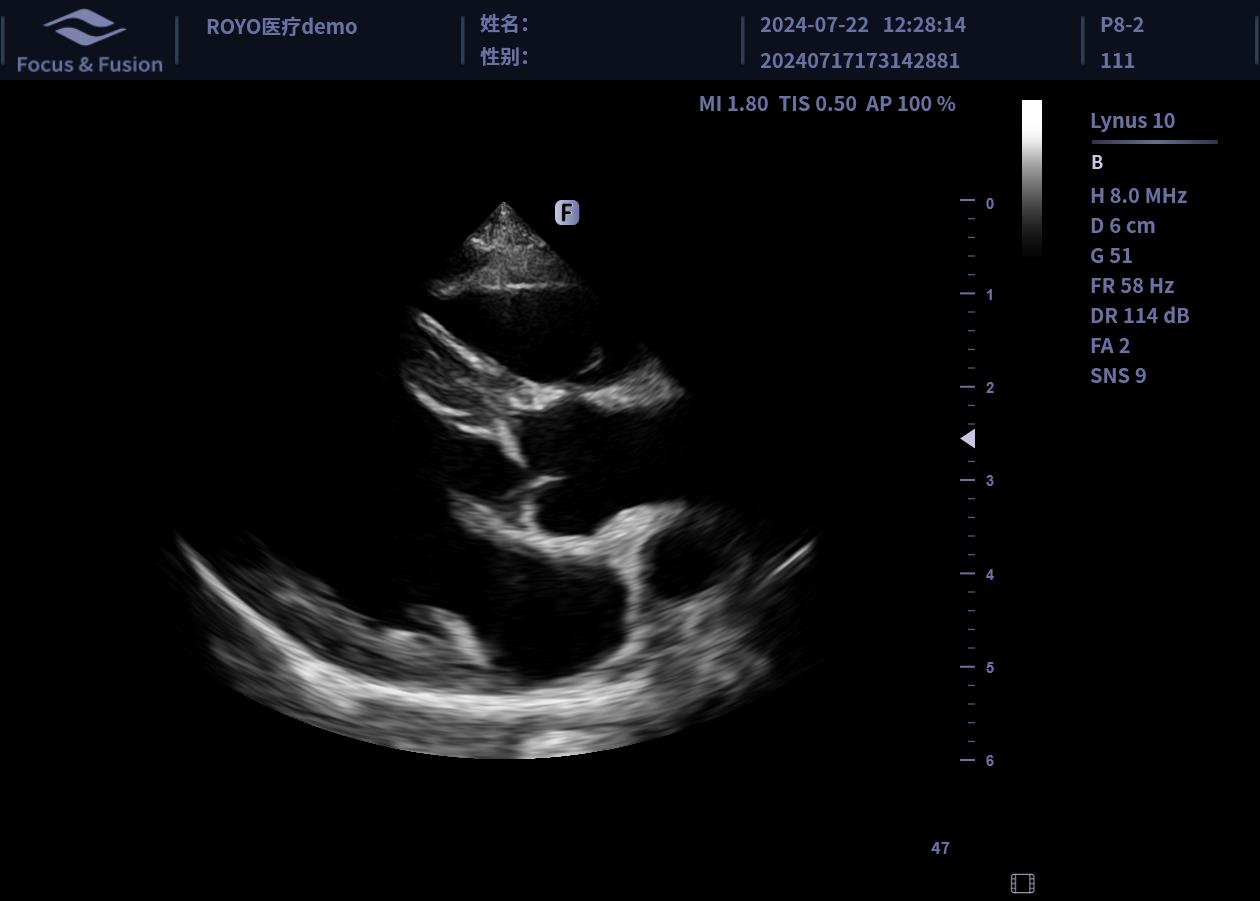

圖片展示

Image List